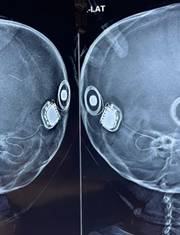

A 2yr old profoundly deaf child underwent simultaneous bilateral cochlear implant surgery with us and got introduced to the magical world of hearing!

#simultaneousbilateralcochlearimplants